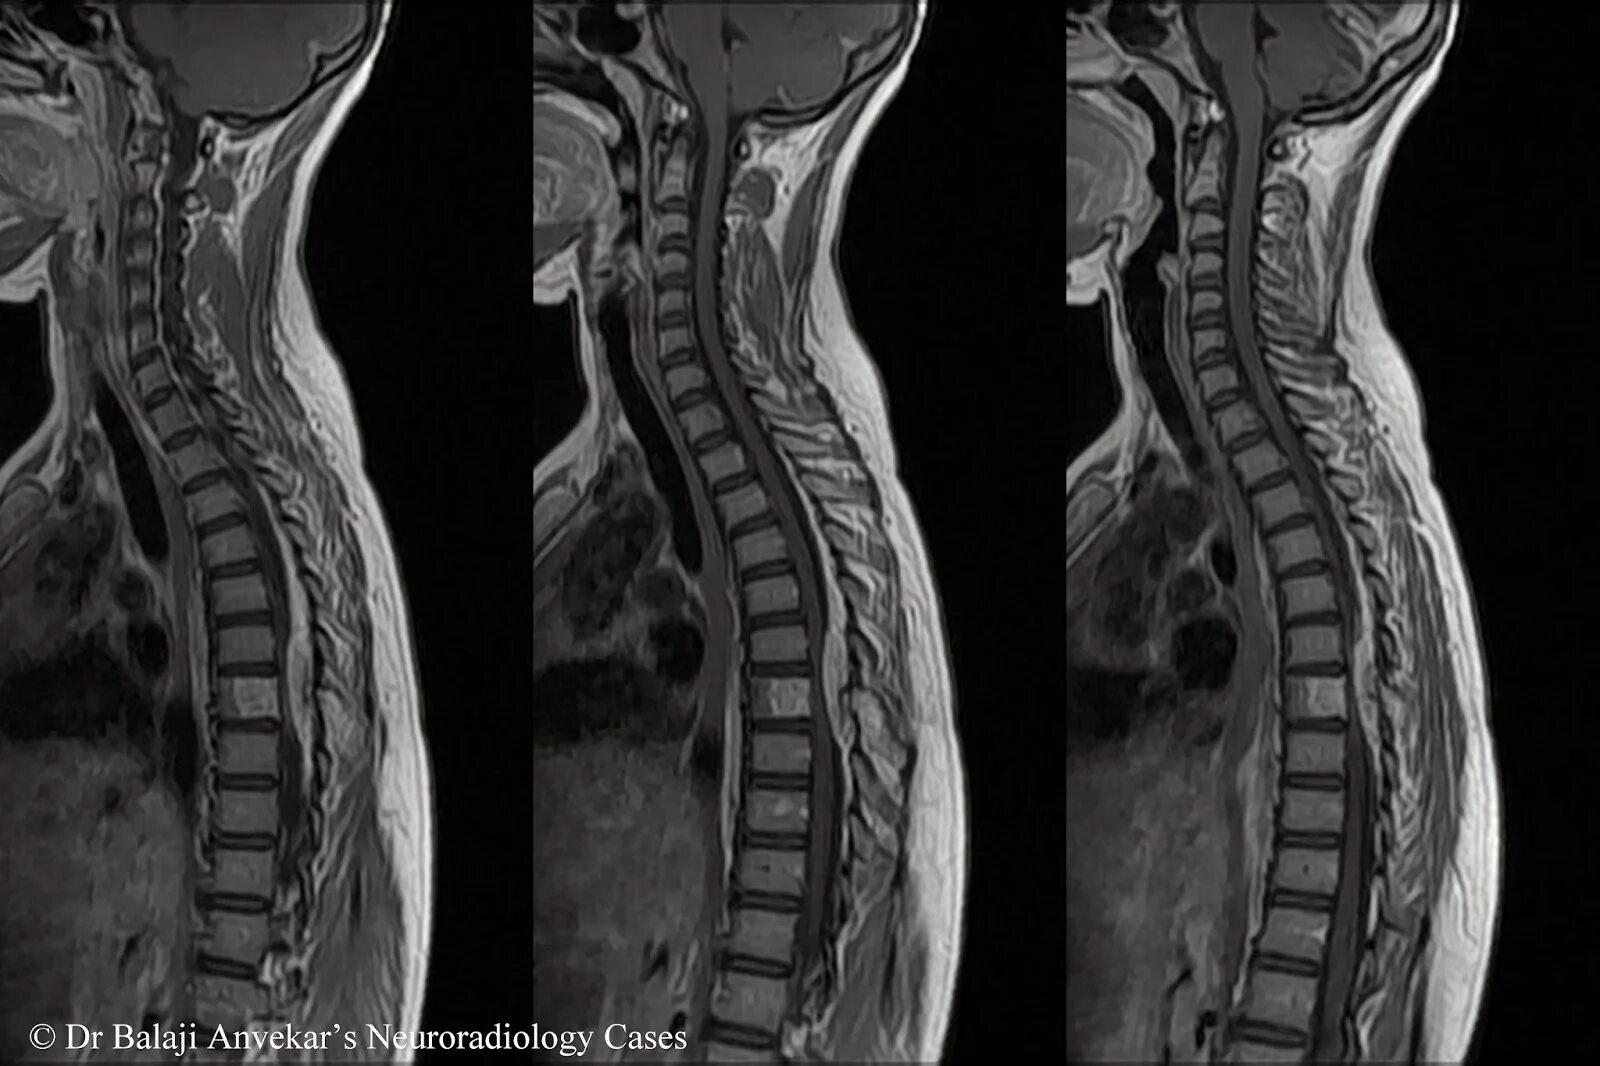

Spine mri